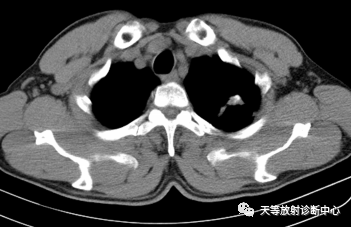

CT平扫:结核瘤通常为直径≥2cm的单发或多发球形高密度影,多呈圆形、类圆形;亦圆有呈轻度分叶状者,边缘多清楚规整,少数模糊,密度多不均匀,多数可见钙化;有空洞者不少见,空洞为边缘性,呈裂状或新月状,结核瘤周围,一般在外缘可见毛状或胸膜粘连带,大多数病例可见卫星灶,有的病例可见引流支气管。增强扫描显示结核瘤或结节具有特征性表现。

▲周围型肺癌:肿块类圆形,生长较快,具有向肺门方向生长趋势(与支气管匍匐征类似)

明显强化,局部包绕侵犯血管。